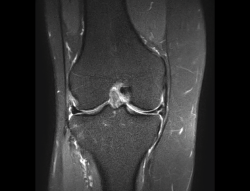

1.2. Ligamentos

Se visualizan como estructuras lineales hipointensas en todas las secuencias.

1.2.1. Ligamentos laterales

Figura 36. Corte de secuencia coronal T2 Fat-Sat: ligamentos colaterales normales.

Ligamento lateral interno (LLI) y ligamento lateral externo (LLE) (Figuras 36, 37, 38 y 39).